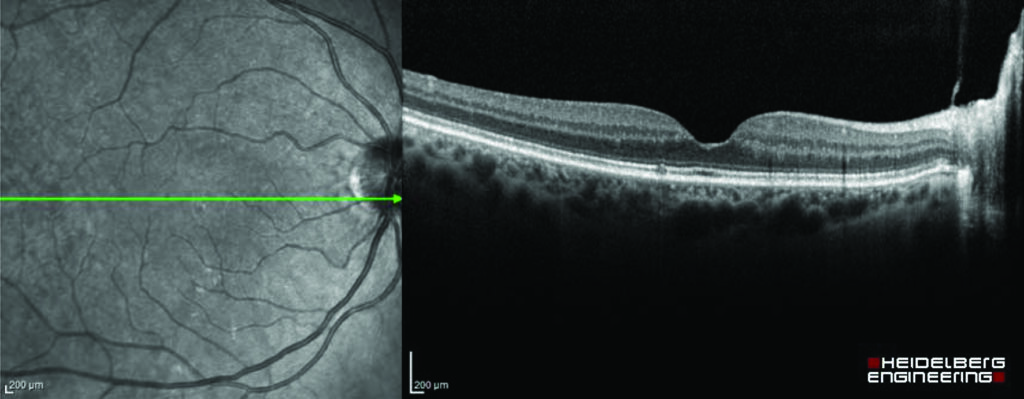

What is an eye scan?

A scan is a visual way of viewing and measuring the inner layers of your eye. The scans can diagnose conditions that are not visible on the surface of the eye and can help to monitor the progression and treatment of the condition.

OCT (optical coherence tomography) scans are the most common types of scans, but you may also have other scans while visiting the eye clinic. All the scans are painless and non-invasive, although we may need to gently lift up your eye lids. The scans only take a couple of minutes.